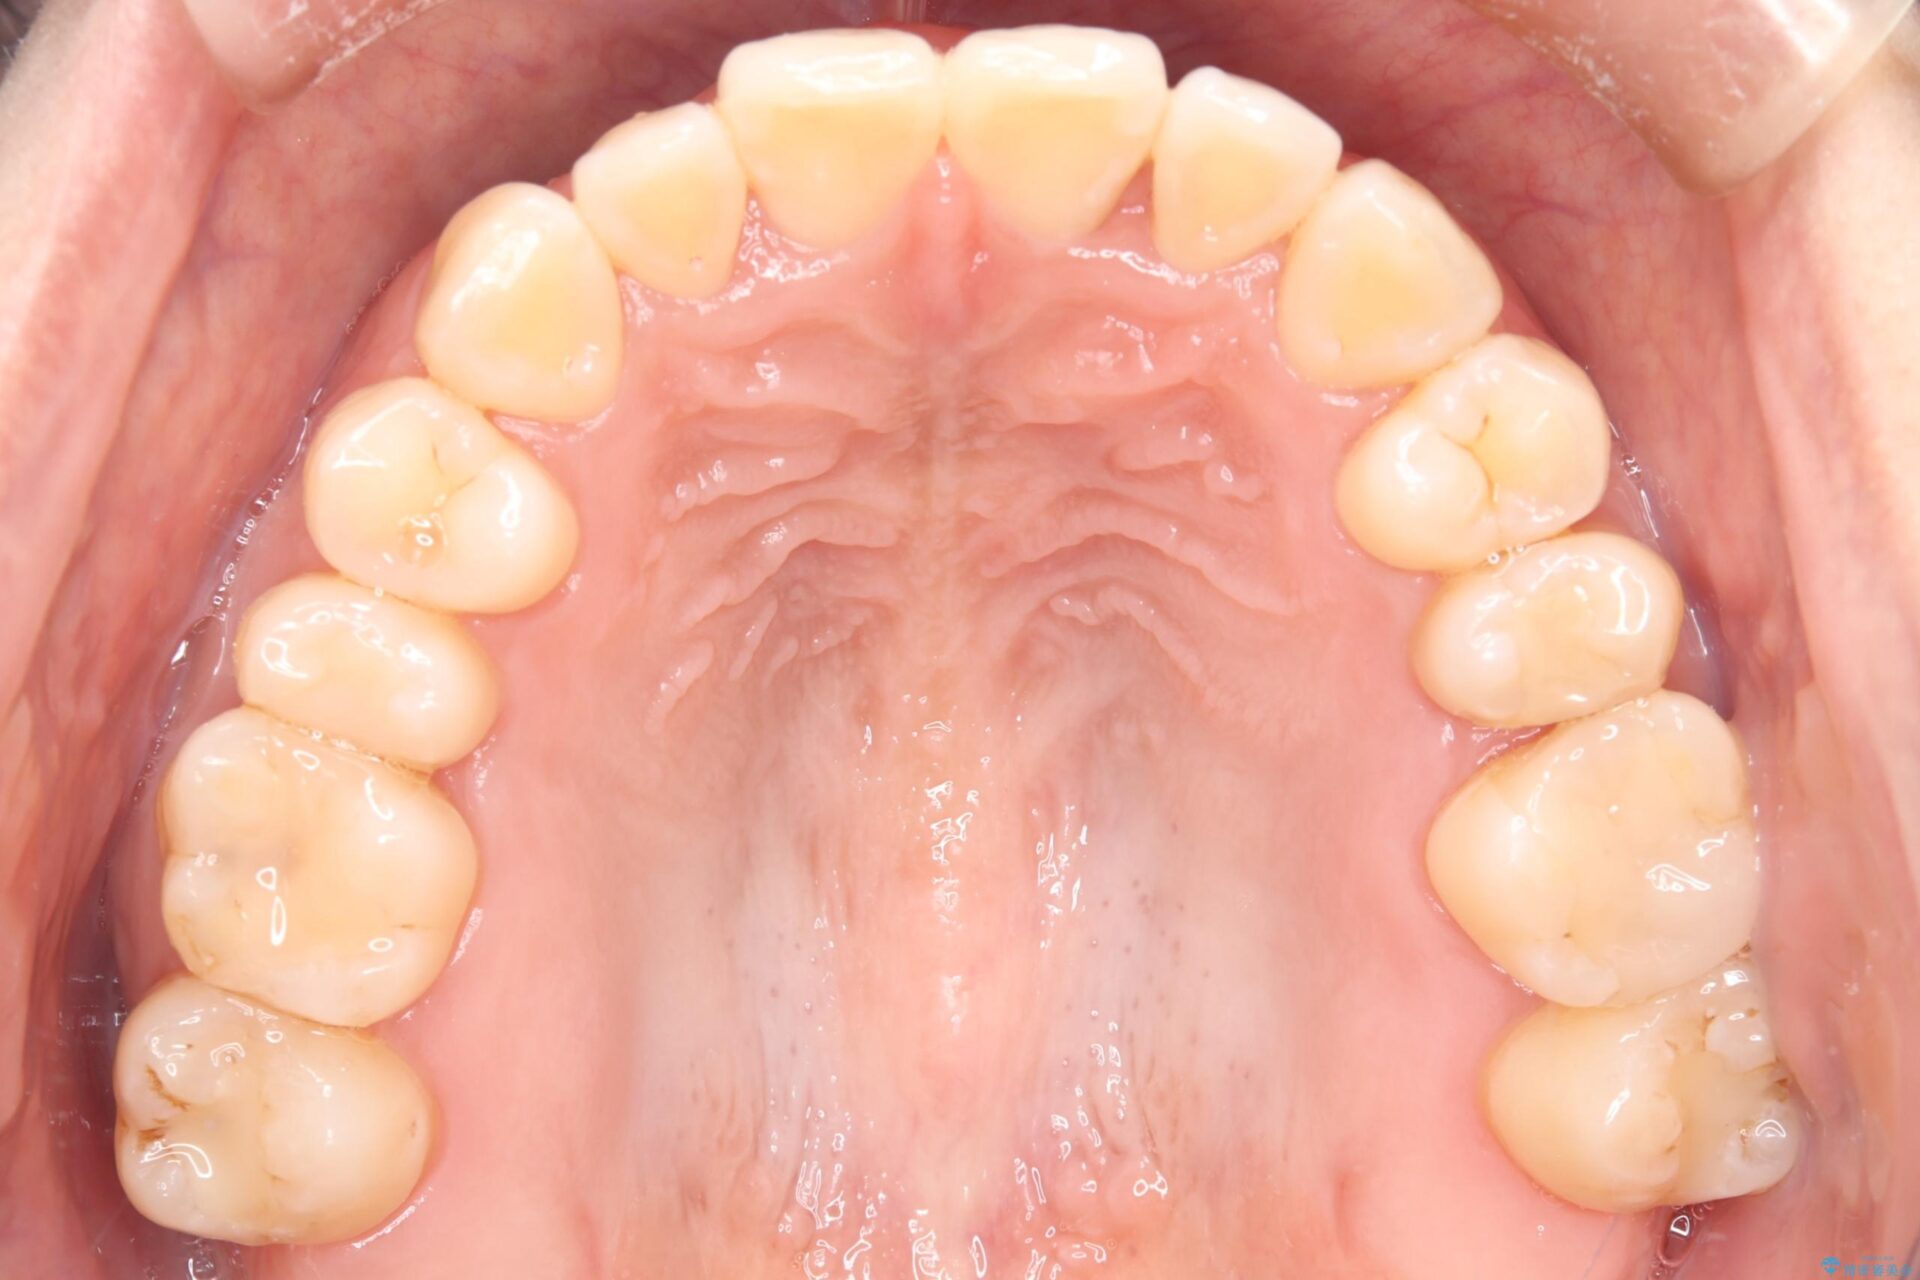

治療後について

かみ合わせを整えるためにゴム掛けも併用して治療を行いました。

患者様にマウスピースの使用とゴム掛けを頑張っていただいたおかげでリファイメント(マウスピースの再発注)も1回で終了することができました。